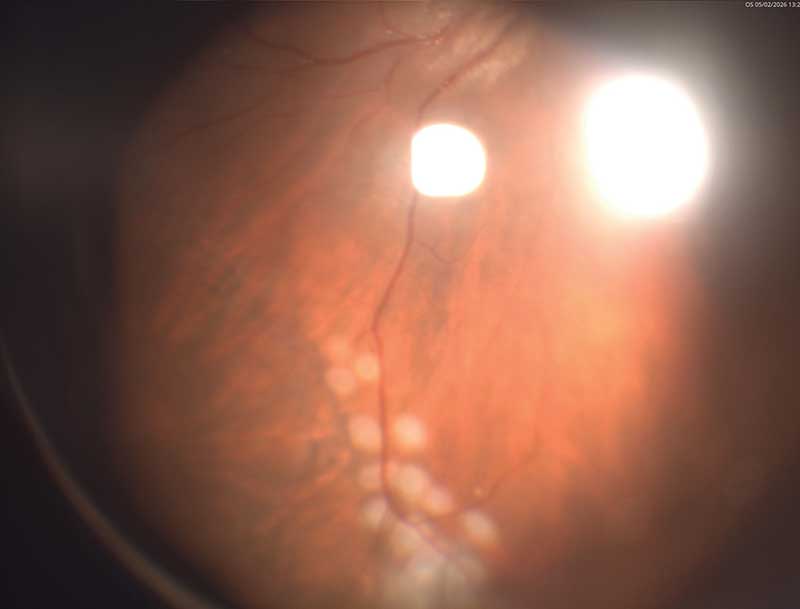

Рис. 1. Фото глазного дна левого глаза после первого этапа операции (тампонада силиконовым маслом; в верхненаружном квадранте визуализируется зона бывшего ретиношизиса, отграниченная лазеркоагулятами)

На первые сутки после операции МКОЗ левого глаза составила 0,2. Сетчатка прилежит во всех отделах, зона ретиношизиса и разрыв блокированы лазеркоагулятами. Офтальмогипертензия (ВГД OS – 28 мм рт. ст.) купирована с помощью инстилляций гипотензивных капель. Пациент выписан на вторые сутки под амбулаторное наблюдение с соответствующими рекомендациями (рис. 1 и 2).

Во время контрольных осмотров через четыре, шесть и 12 недель отмечалась стабильная картина: МКОЗ OS – 0,2, сетчатка прилежит, зона ретиношизиса не определяется, ВГД в пределах 21–25 мм рт. ст. на фоне инстилляций гипотензивных препаратов. На одном из осмотров пациент дополнительно сообщил о травме левого глаза веткой около полугода назад (за медицинской помощью не обращался). В связи с этим повторная госпитализация для удаления силикона была отложена (динамическое наблюдение).